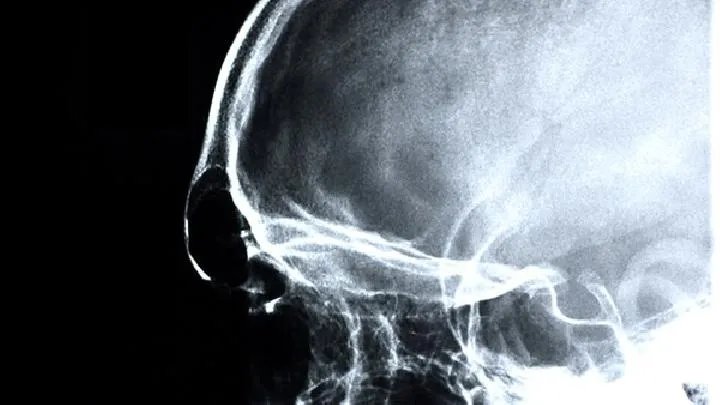

的有关信息介绍如下:小孩脑瘫的症状有哪些?脑瘫疾病的早期症状表现并不是非常明显,但若是能重视身体检查的情况下,发现早期的脑瘫其实也并不困难,应该有所了解的是,对脑瘫疾病来说,能否及时治疗是很关键的一个方面,下面就脑瘫的症状进行介绍: